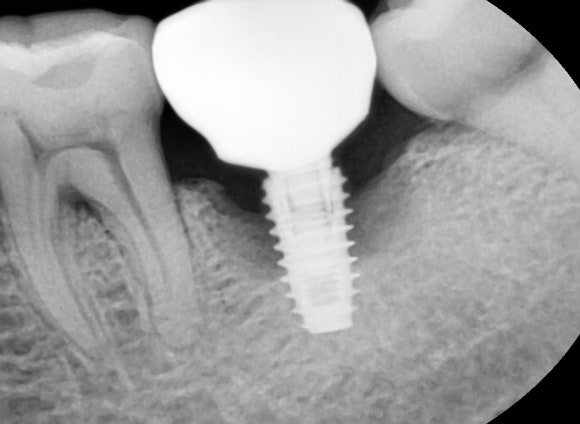

임플란트는 뼈와 인공 치근(티타늄)이

단단히 붙는 ‘골유착’ 과정이 꼭 필요합니다.

이편한세상치과는 속도보다 ‘안정성’을 우선으로 하고 있는데요.

잇몸이 약한 분이라 뼈이식을 동반해서 치료해 드렸습니다^^

촬영일 : 241206

뼈 상태가 좋다면 빠른 시술도 가능하지만,

염증이 있거나 잇몸이 약한 경우라면

충분한 회복 시간을 두고 단계별로 접근합니다.

조금 시간이 걸리더라도

한 번 심은 임플란트가 오래도록 제 역할을 하는 것이

진짜 성공적인 치료라고 믿기 때문입니다.